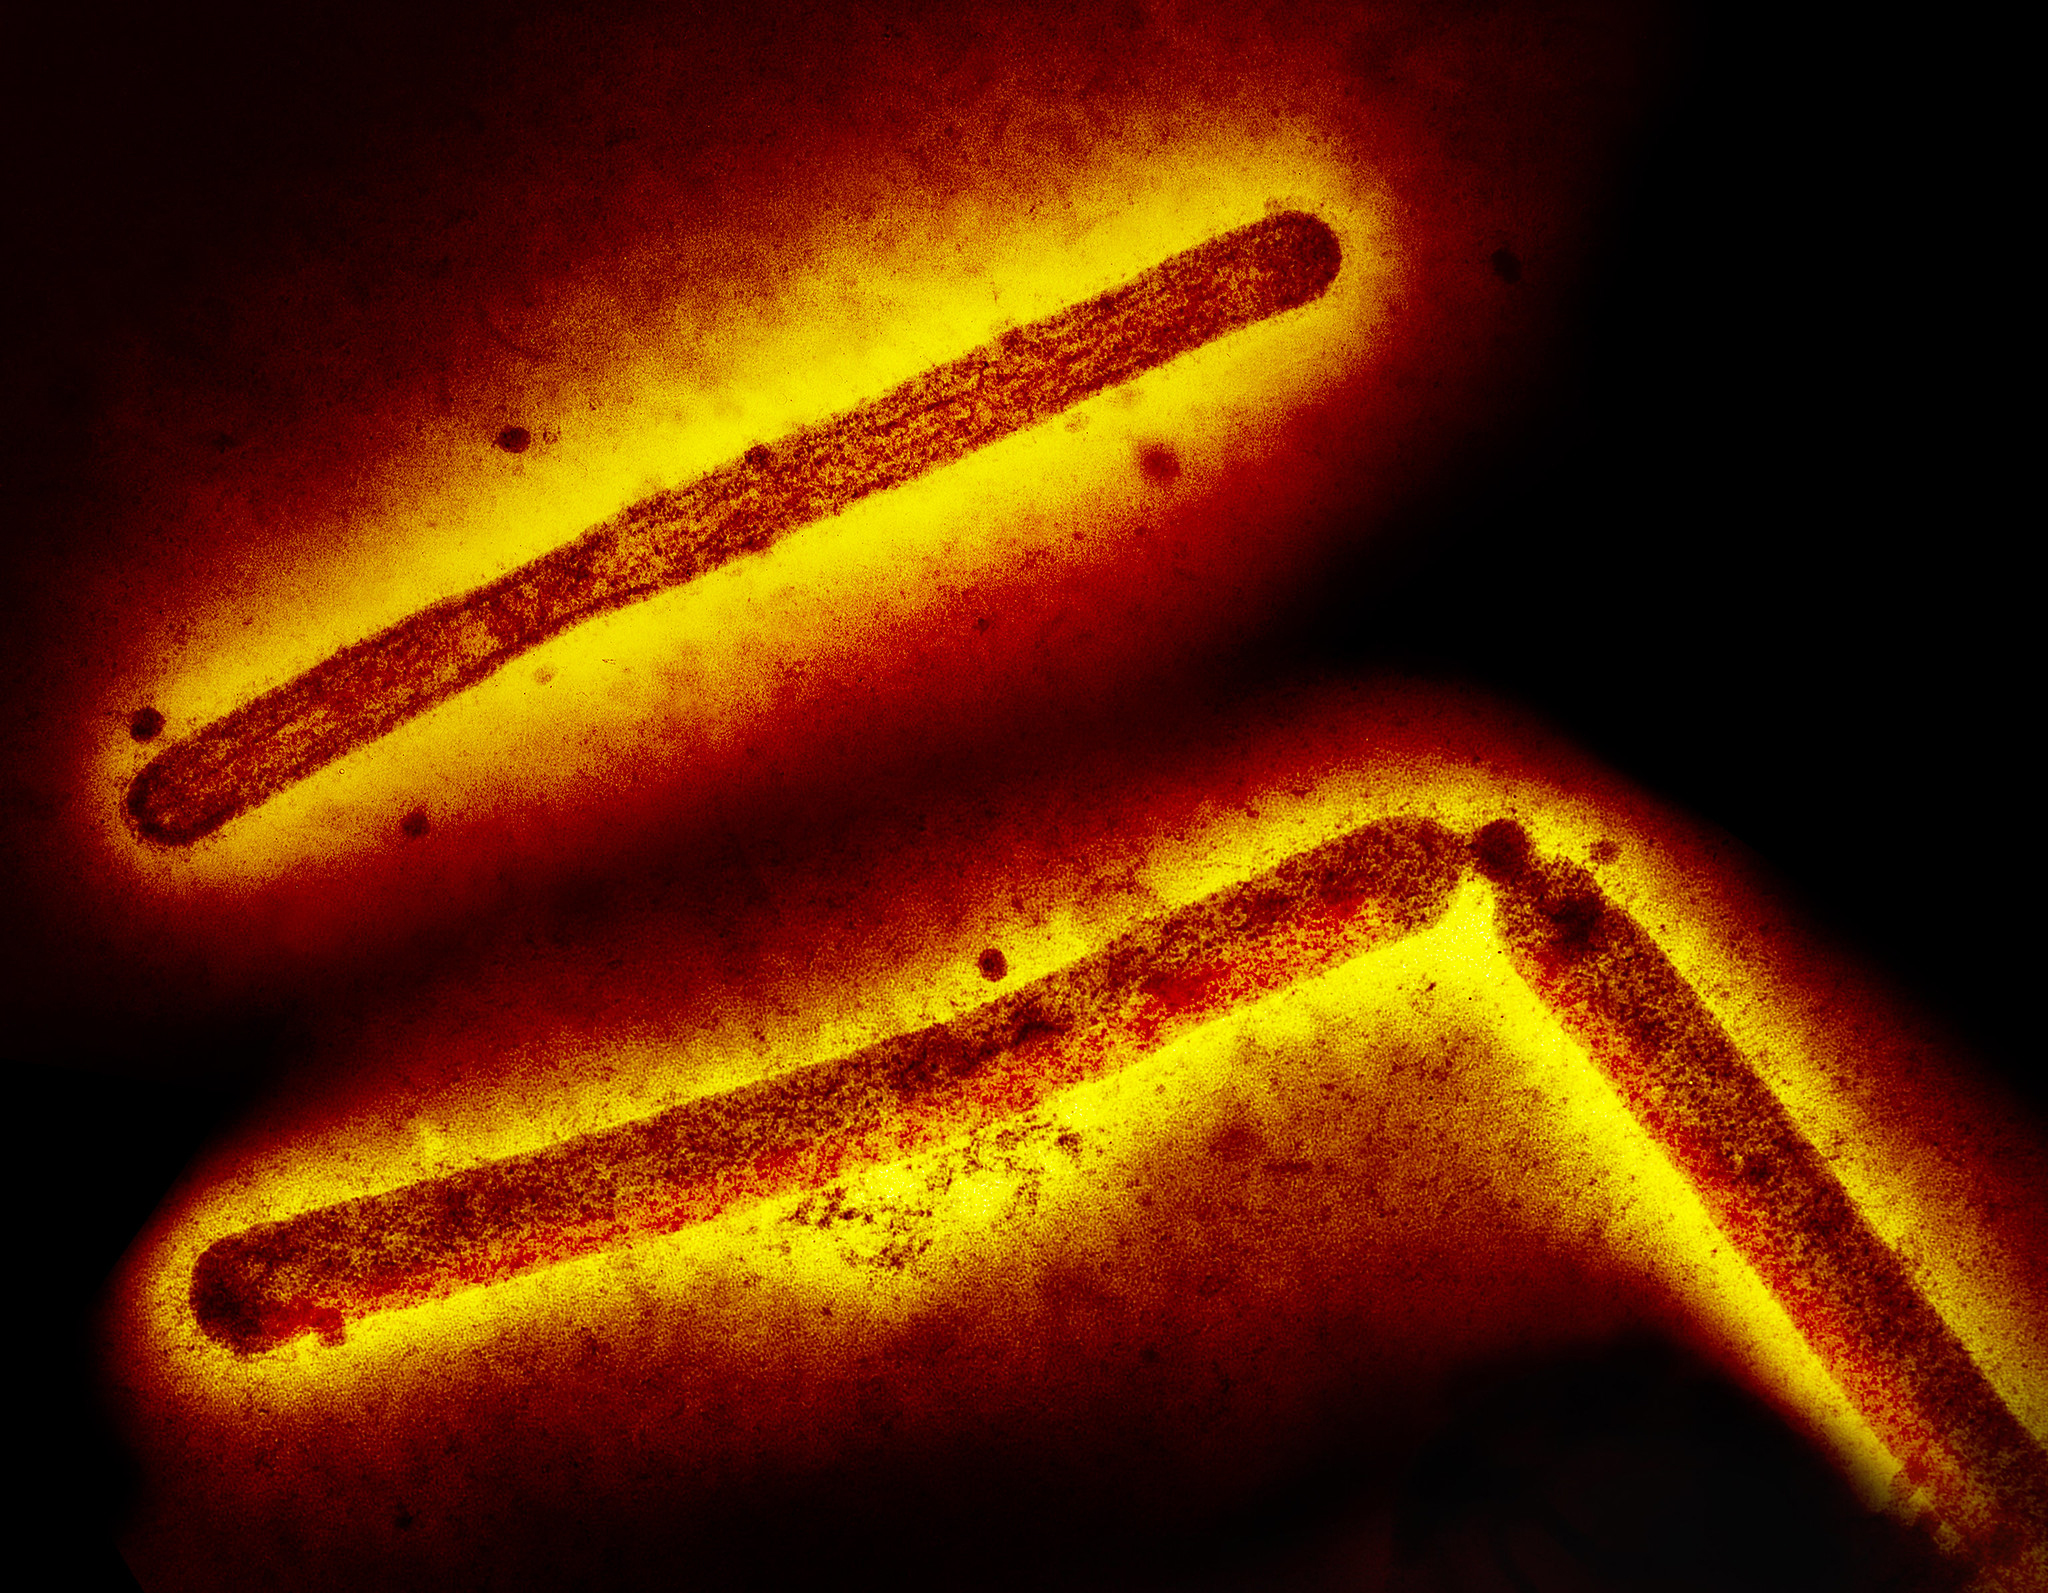

National Institutes of Health (NIH) scientists and their colleagues report that a single dose of a broadly neutralizing antibody (bnAb) administered prior to virus exposure protects macaques from severe H5N1 avian influenza. Highly pathogenic avian influenza (HPAI) H5N1 viruses have sporadically spilled over from birds into many other animals, including humans and dairy cows, in recent years. Although it has not yet acquired the capacity to spread readily between people, H5N1 has pandemic potential, which has spurred efforts to develop effective treatments and other countermeasures.

The investigators studied a bnAb called MEDI8852, which was discovered and developed by Medimmune, now part of AstraZeneca. MEDI8852 targets a portion of a key flu protein that is less prone to change than other parts of the virus and thus is capable of conferring protection against a wide range of flu viruses. In the new study, a group of macaques received an injection of MEDI8852 and were exposed to aerosolized HPAI H5N1 virus three days later. All the pre-treated animals survived and experienced no or very limited signs of disease. In contrast, a group of control macaques developed severe or fatal illness within a short time after virus exposure. Of note, the scientists determined that MEDI8852 remained in the body for a prolonged time after the injection. According to scientists, protection from severe disease would extend to weeks beyond antibody infusion, providing a realistic preventative window in the face of an H5N1 outbreak.